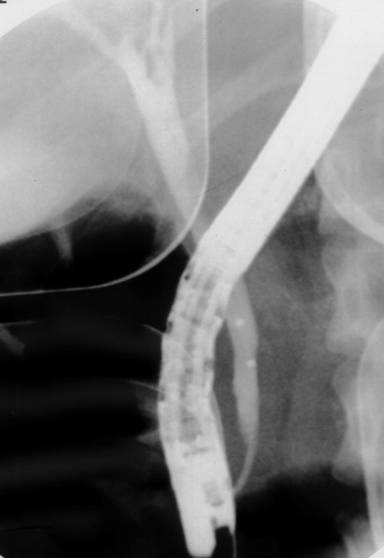

A 33-year-old healthy woman was born and lives in Bangkok which is the largest urban area of Thailand. She works as a secretary of a private company. She loves eating fresh vegetables. She had the history of intermittent epigastric pain for two months and presented with severe abdominal pain radiating to her back with nausea and vomiting for one day. Physical examination revealed febrile (37.5°C), no jaundice, marked tenderness at epigastrium and decreased bowel sound. Laboratory testing results showed leukocytosis of 11.7 x103/µL (reference range: 4.0-11.0 x103/µL) with 72% granulocytes (reference range: 40-74%) and 3% eosinophil (reference range: 0-7%), AST 105 U/L (reference range: 0-40 U/L), ALT 157 U/L (reference range: 0-40 U/L), alkaline phosphatase 229 U/L (reference range: 32-92 U/L), total bilirubin 1.4 mg/dL (reference range: 0.3-1.2 mg/dL), direct bilirubin 1.0 mg/dL (reference range: 0-0.5 mg/dL) and serum amylase 2,036 U/L (reference range: 0-220 U/L). Stool testing for parasites and ova were negative for three days. Abdominal computed tomography (CT scan) showed dilated common bile duct (0.8 cm in diameter) without filling defects and no gallstone. No evidence of acute pancreatitis was found from this study. She was initially diagnosed with acute mild gallstone pancreatitis with suspected retained common bile duct stone by over all clinical manifestations. Endoscopic retrograde cholangiography was performed and swollen ampulla with purulent bile were noted (Figure 1). Cholangiogram showed dilated common bile duct of 1.2 cm and there was a cylindrical filling defect about 6-7 cm in length inside the common bile duct (Figure 2). After endoscopic sphincterotomy, the parasite popped out and was extracted, using an extraction balloon catheter, then removed with a snare. The cholangiogram after removing this parasite showed markedly decreased in size of common bile duct without residual filling defect. The parasite in duodenum was shown in Figure 3. It was identified as a 22 cm long adult form of Ascaris lumbricoides (Figure 4).

Figure 2. The cholangiogram after removal of parasite showed decreased size of common bile duct without filling defect. |